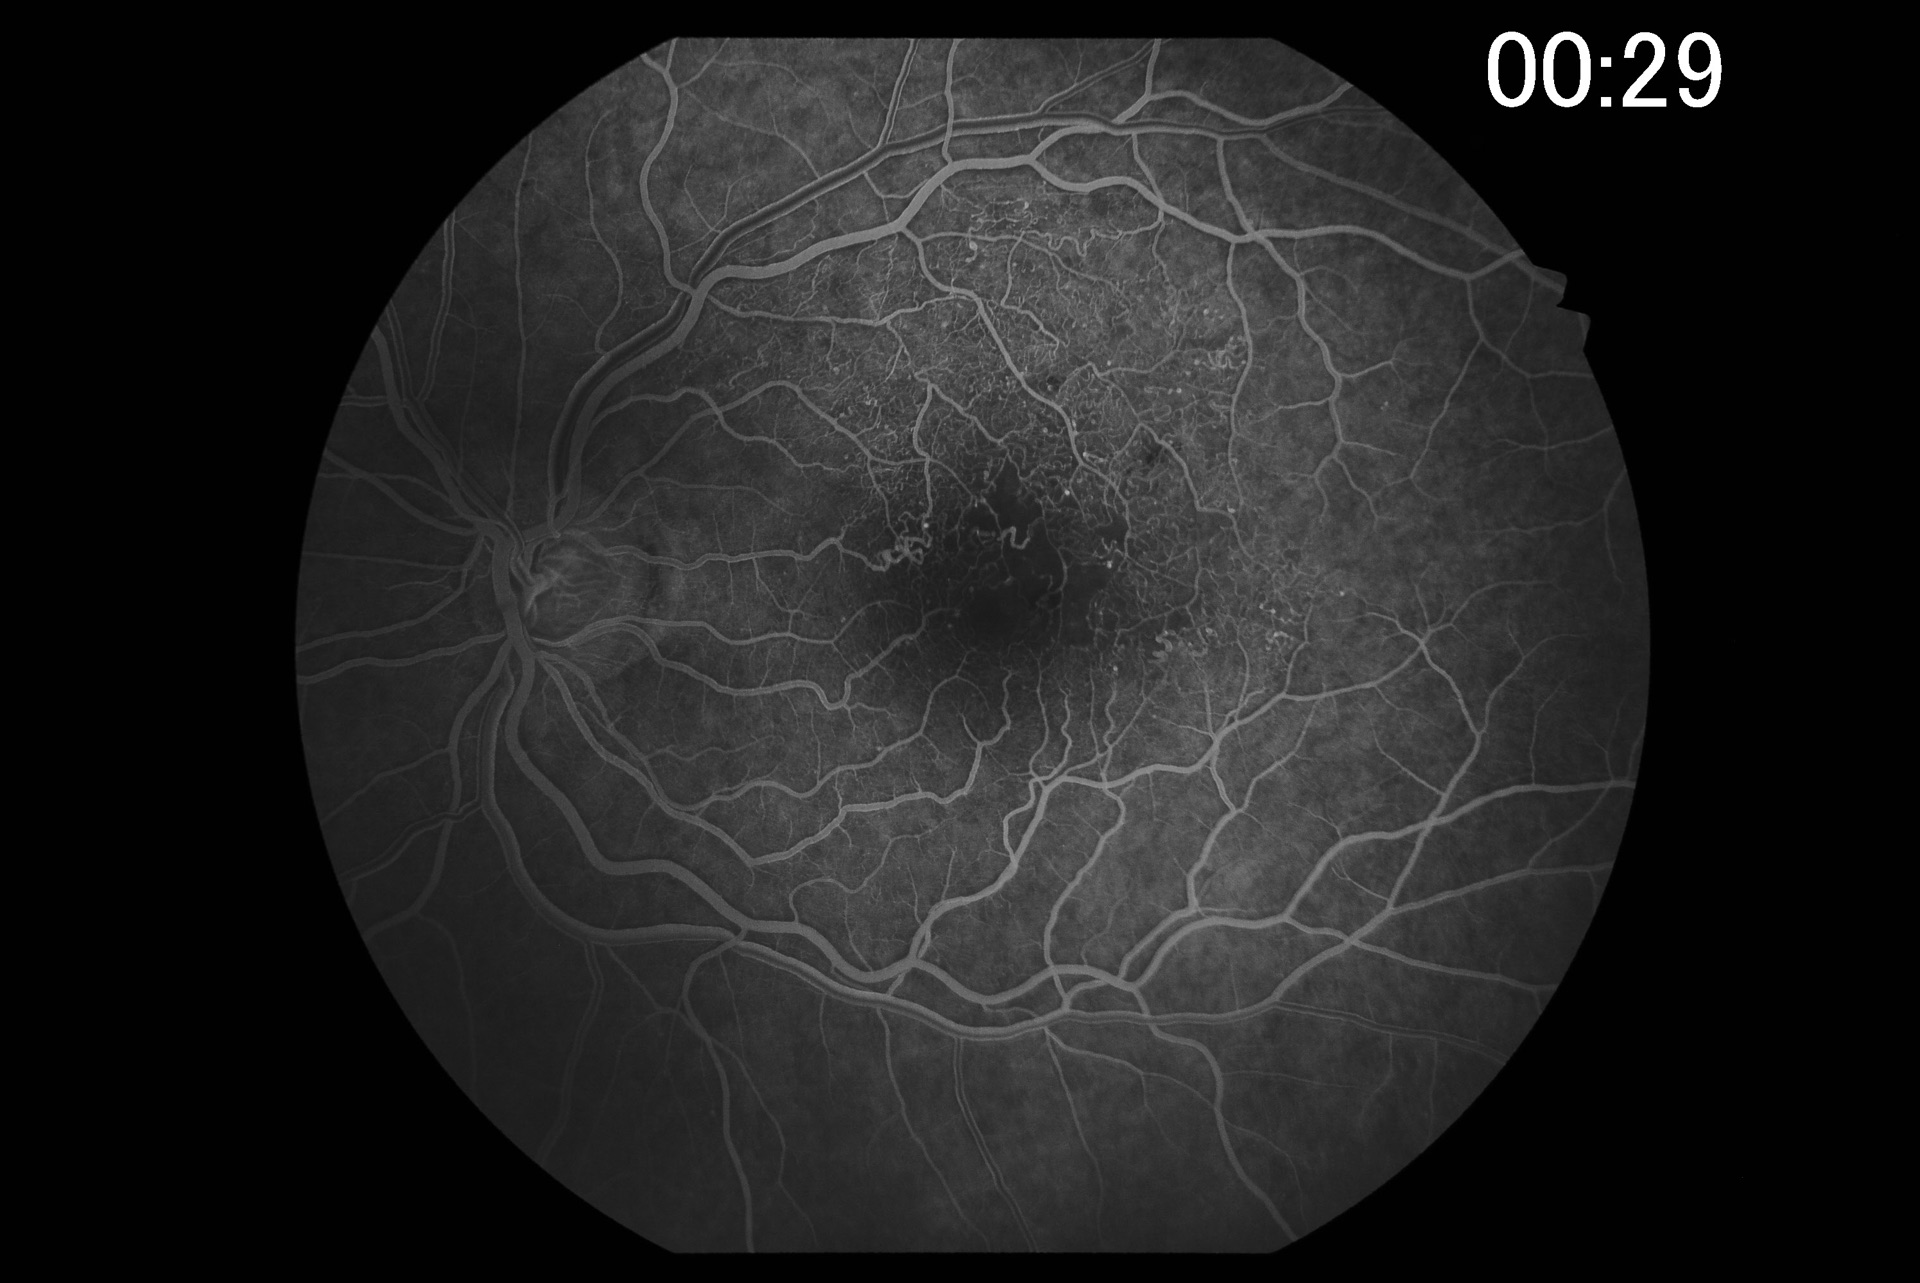

Powerful digital imaging software VK-2

With the digital imaging software VK-2, retinal images captured with the Kowa retinal camera, but also images from other sources, such as a scanner, are captured and stored quickly and easily. The input of video signals via USB is supported by switching between the instruments with 1 click. Images can be enlarged for viewing and filters (e.g. red-free filters) are available. In FA mode, the time information for each patient is displayed on the screen and several timers are available for different patients. The assembly function creates panoramic images from several fundus images.